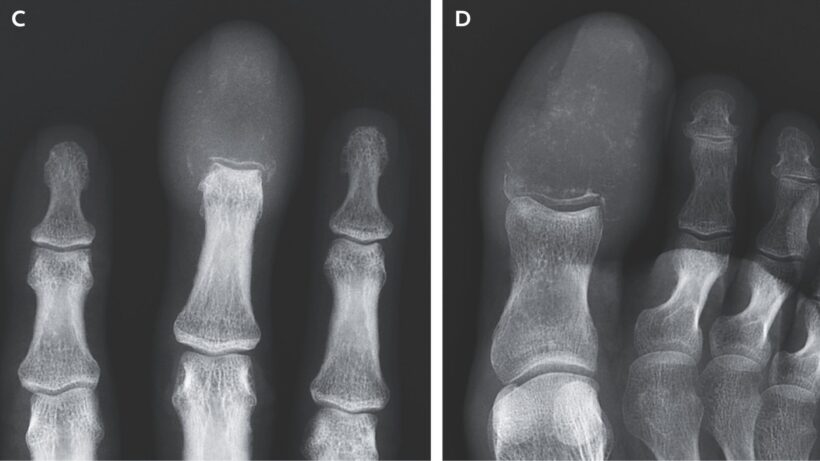

Результаты КТ и МРТ показали «деструктивные литические поражения», полностью разрушившие костную ткань в кончиках пальцев. Литические поражения — это участки кости, разрушенные патологическим процессом, чаще всего злокачественным.

Метастазы в костях пальцев могут имитировать подагру или остеомиелит, но рентгенография позволяет отличить эти состояния. Подагра — форма артрита, а остеомиелит — воспаление костей, обычно инфекционной природы. Оба заболевания сопровождаются отёком и покраснением.

На основании снимков мужчине диагностировали акрометастазы — редкую форму метастазирования в кости дистальных отделов конечностей (ниже локтей или коленей). Согласно обзору 2021 года, акрометастазы составляют всего 0,1% случаев костного метастазирования.